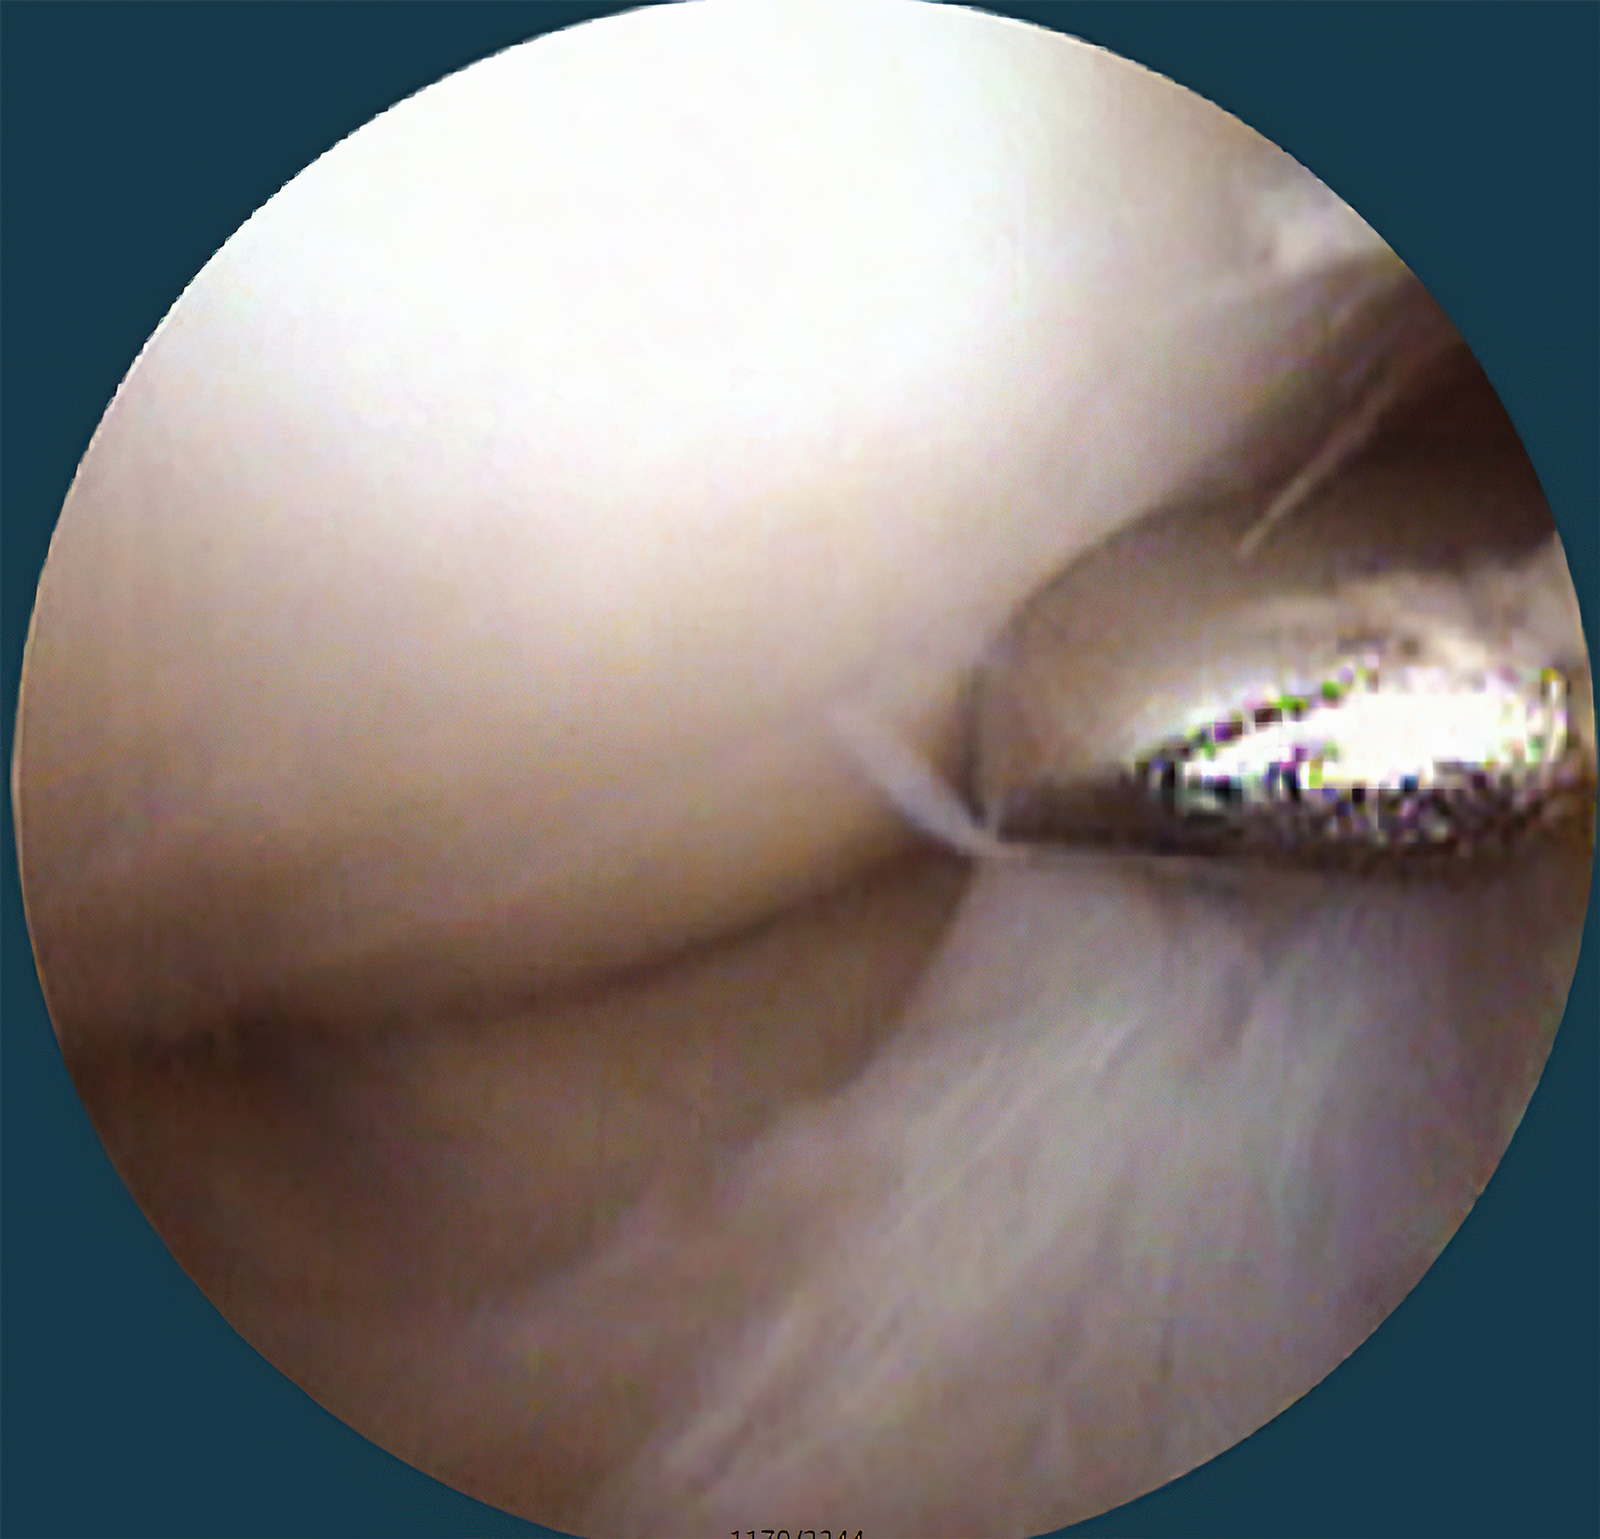

医生可通过关节镜观察患者关节内情况

关节镜手术因具有创伤小、恢复快等特点,被广泛应用于各种关节疾病的诊断和治疗。像膝关节软骨、半月板、韧带的损伤以及各种滑膜炎,都可以通过关节镜来治疗。

关节腔内游离体

关节镜下清理术内容包括不断地大量冲洗、去除增生的滑膜以及骨赘、去除多余的脂肪组织、修整关节面、修复半月板、去除游离体等,解决患者存在游离体、半月板撕裂移位、骸骨轨迹不良、滑膜病变、软骨面不适合等问题。